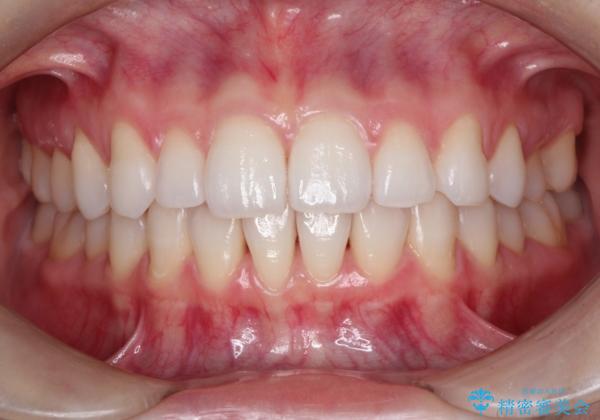

インビザラインで出っ歯を改善する 抜歯をしないinvisalign治療

- 20代女性

- 1年5ヶ月

- 非抜歯・遠心移動による前突の改善をマウスピースにて計画した。

非抜歯矯正の場合、大きく前歯を下げることはできませんが、奥歯の遠心移動や歯のサイズダウンにより歯軸を立て、見かけ上の出っ歯感をある程度改善することができます。